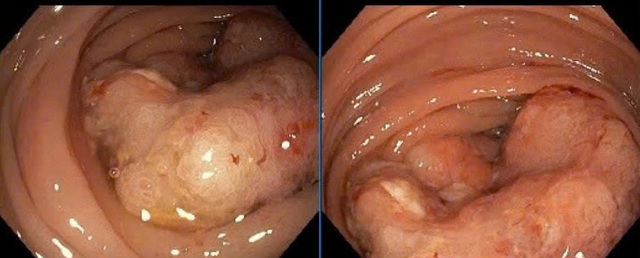

Bệnh nhân nhập viện với thể trạng yếu, bụng chướng, mệt mỏi và khó đại tiện. Qua thăm khám và nội soi, bác sĩ phát hiện khối u đại tràng góc lách lớn, chiếm gần hết lòng đại tràng, nguy cơ tắc ruột cao.

Hình ảnh u đại tràng ở bệnh nhân. Ảnh: BVCC